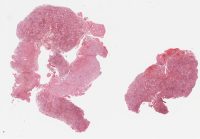

CANP2008-7.svs

70000 x 46723

@ 20X